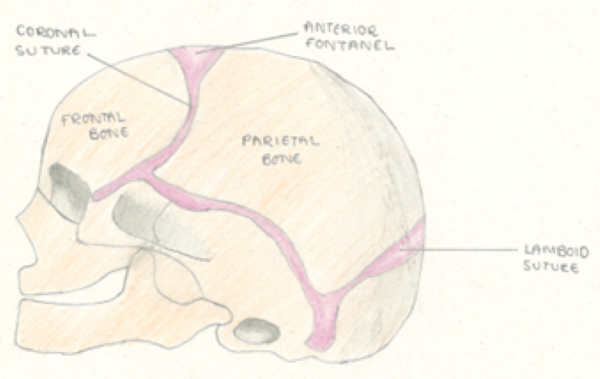

Suture lines in infants

It is common to mistake the suture lines as skull fractures as these can also be seen as disruptions in the periosteum but are not pathological. It is best to be familiar with skull anatomy and the associated suture lines as illustrated in Figure 4.

If in doubt, follow the suture lines from the fontanelles with your finger, scan accordingly then re-scan the area of interest again confirming that what you are identifying is not part of the normal suture anatomy.

Scan the contralateral side in order to confirm that this is not in keeping with the path of the (usually roughly symmetrical) suture lines.

Figure 4. Illustrations of the skull highlighting the anatomical positions of the suture lines

Note in cases of pre-existing positional plagiocephaly suture lines may not follow a symmetrical path on the contralateral skull.